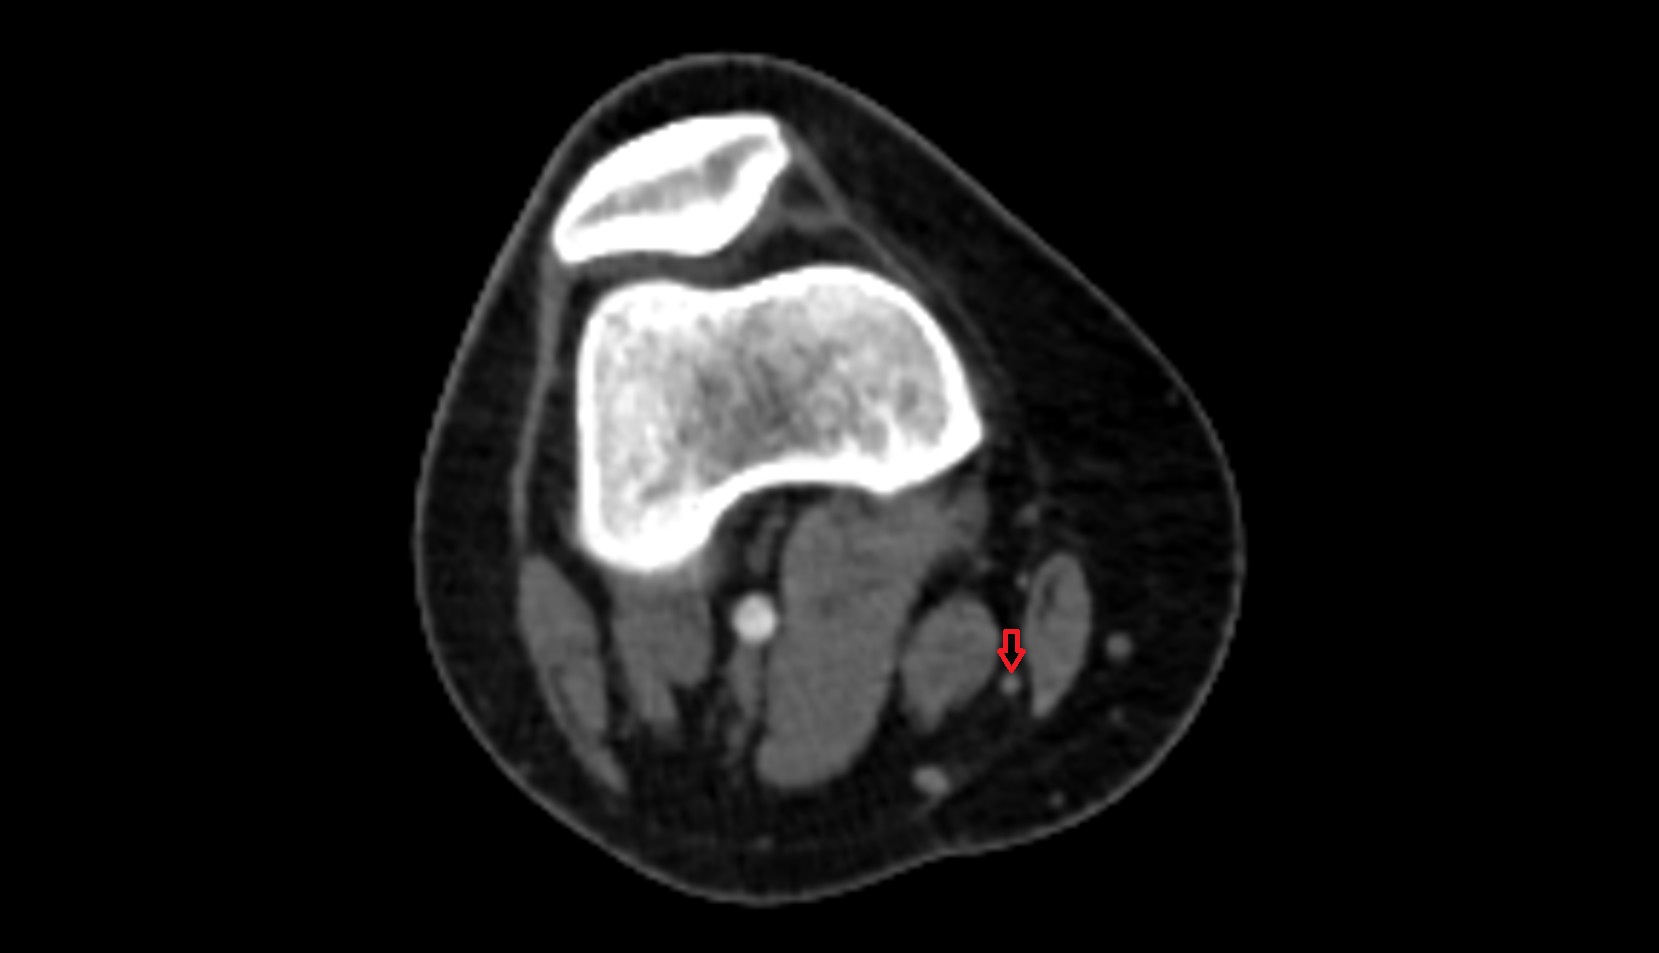

- Popliteal artery

- Popliteal vein